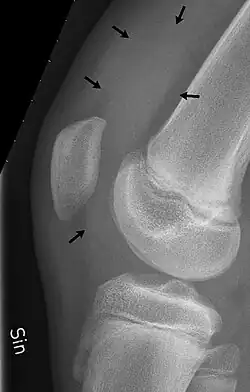

X-ray of the knee of a 12-year-old male, showing knee effusion of medium severity, marked by black arrows. It displaces the patella anteriorly and extends into the suprapatellar bursa.

Magnetic Resonance Imaging detects abnormalities of the bone or knee joint, such as damage to the ligaments, tendons or cartilage. Some injuries that include soft tissue damage that cannot be seen on X-Ray may require an MRI.[11]